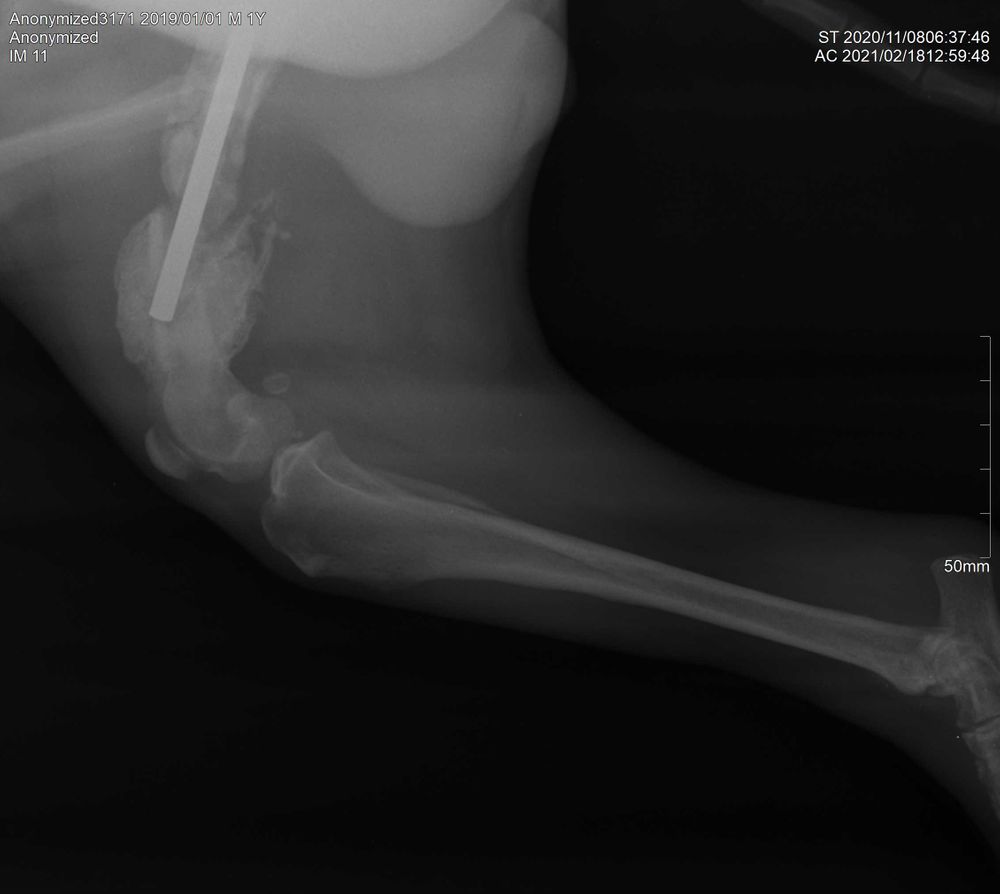

Собаки. Болезни, прививки, советы по уходуПомогите пожалуйста понять по снимкам что происходит. Собаку сбила машина. В октябре сделали операцию. Сделали наруж. Спицы. В конце ноября повторно сделали операцию т.к. повторно сломалась кость. Слелали внутр.спицу. Незаживала рана поверхностная. В феврале зашили ранку положили 2шва. Вздулась нога как при переломе было в первый раз. На след.день настояла на том чтобы швы сняли. Воспаление прошло. Рана на данный момент такая. Интересует один вопрос что делать. Помогите. Не возможно понять на последнем снимке кость разлогается или это обрастает косная мозоль .

Озвучьте врача, можно в личку. Породу, возраст, вес, пол животного, начальный снимок и где вы живёте.